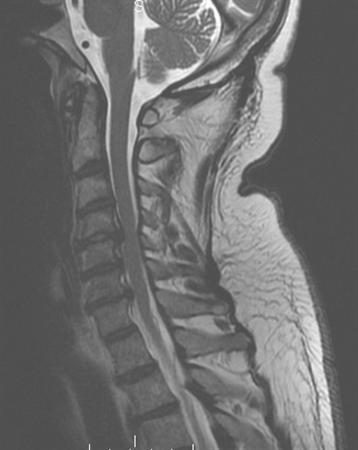

7. A 23-year-old man falls down a flight of stairs while intoxicated and is brought to the emergency room the following morning. On physical exam he has no motor function in his upper and lower extremities. Sensory exam shows diminished but present sensation in the perianal area and in the lower extremities. Reflex exam shows his bulbocavernosus reflex is intact. The inital CT and MRI are seen in Figures A and B. According to the American Spinal Injury Association (ASIA), how would this injury be classified?

FIGURES: A

B

DISCUSSION: This patient has some sensory function but no motor function below the injury level. His bulbocavernosus reflex is intact so we know he is no longer in spinal shock. Therefore, he would be classified as an ASIA B.

The imaging studies show a type II odontoid fracture, a congenital fusion at C2/3 and C4/5, and a large soft disc herniation at C3/4 with spinal cord compression and myelomalacia.